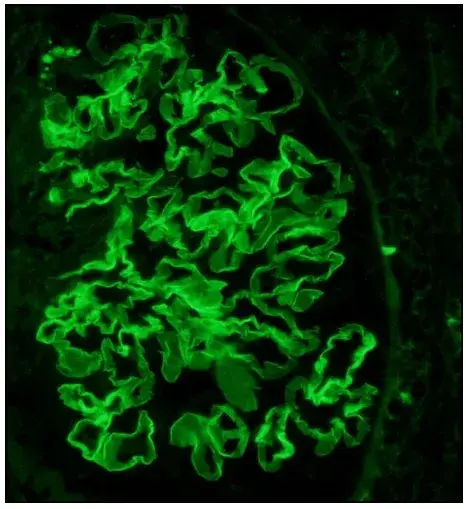

Neste vídeo, abordamos estratégias para lidar com pacientes com nefropatia membranosa que não respondem ao tratamento inicial. Ele enfatiza a importância da reavaliação constante e do ajuste do regime de tratamento com base nos resultados e no estado do paciente.

Como fazer o tratamento da Nefropatia Membranosa de forma prática!

Como fazer o tratamento da Nefropatia Membranosa de forma prática!